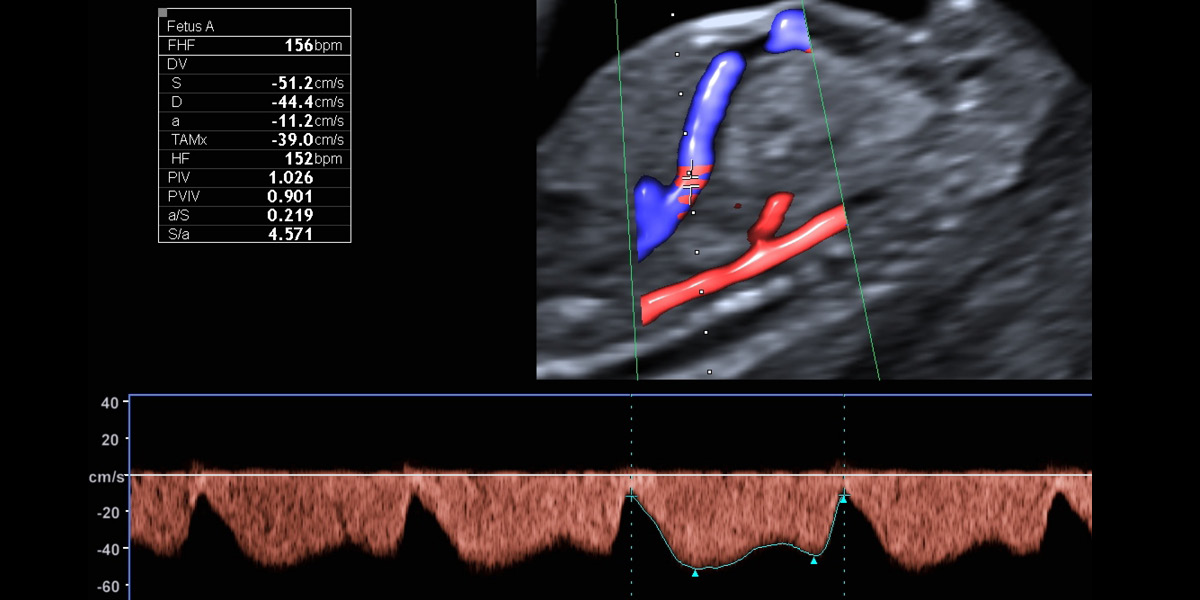

Mit der Nabelschnur fließt der Sauerstoff vom Mutterkuchen direkt ins kindliche Herz. Das Blutflussmuster zeigt einen normalen Fluss, so ist die Wahrscheinlichkeit für Herzfehler und die Trisomie 21 gering.